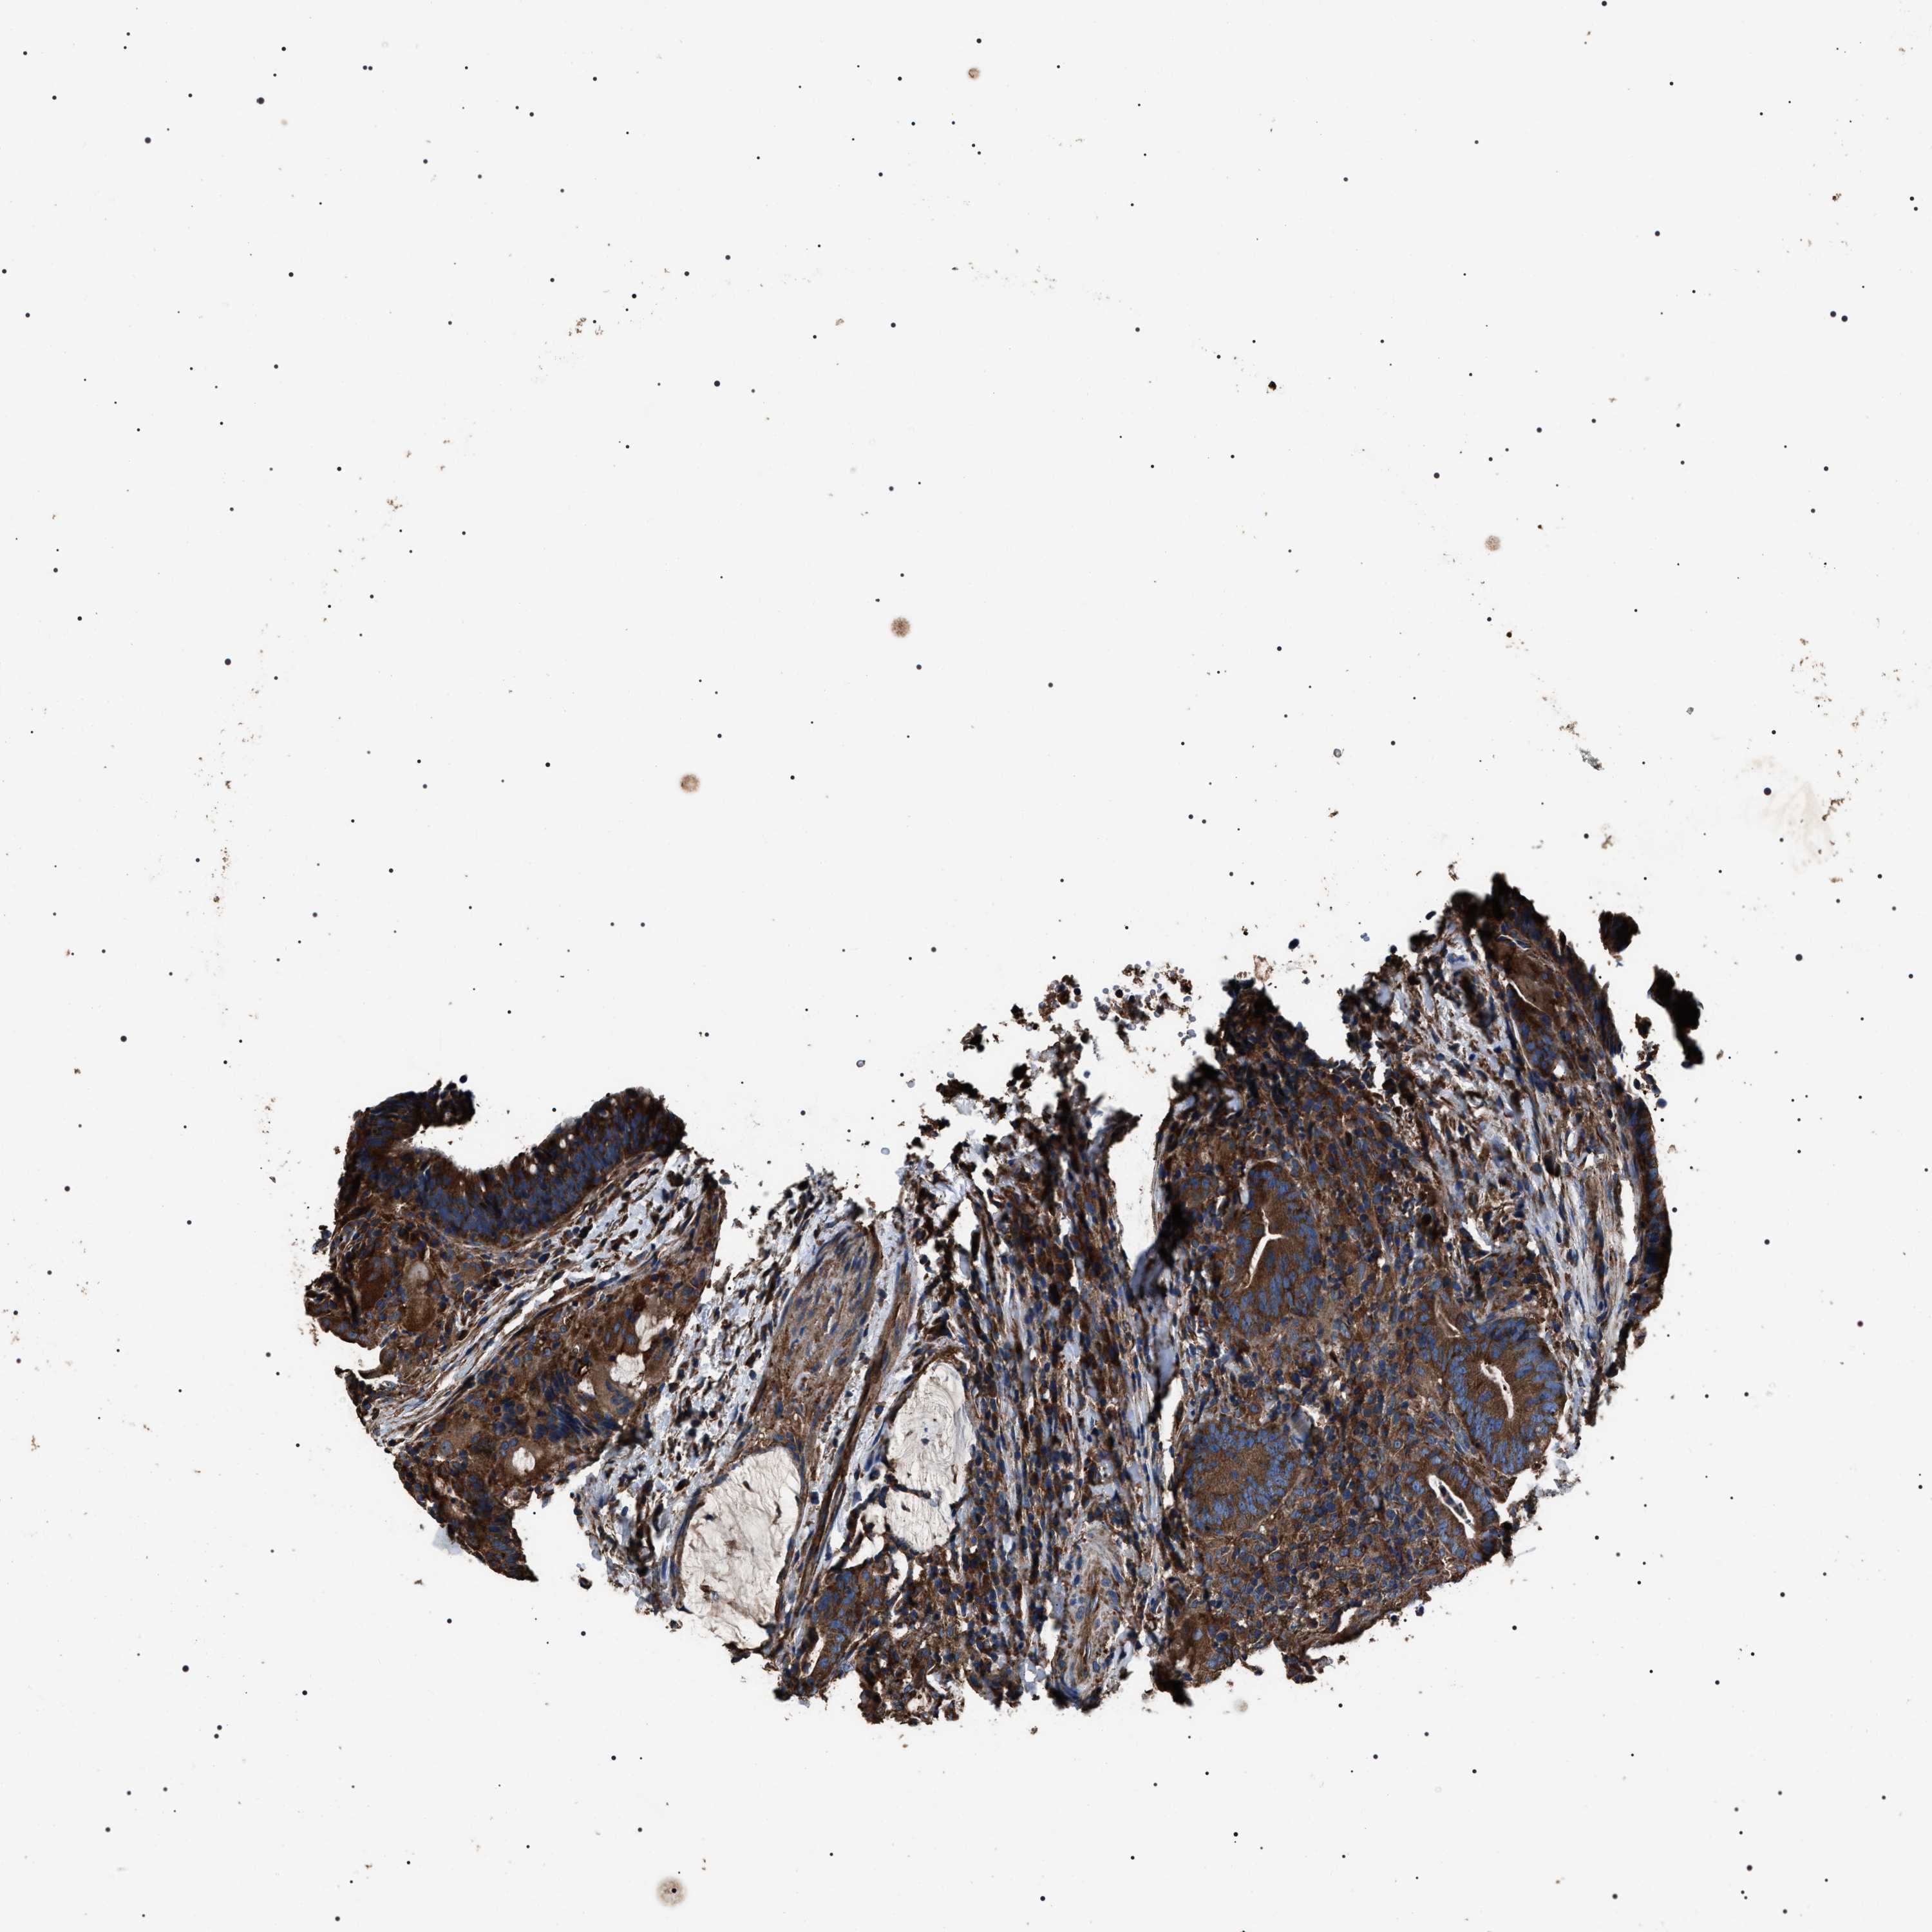

CANCER COLORECTAL CANCER Show tissue menu

ANTIBODIES

AND

VALIDATION

Colorectal cancer

Human cancer

Colon adenocarcinoma

Rectum adenocarcinoma